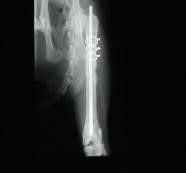

• Bone fracture repair

• Fractured femur repair in a cat